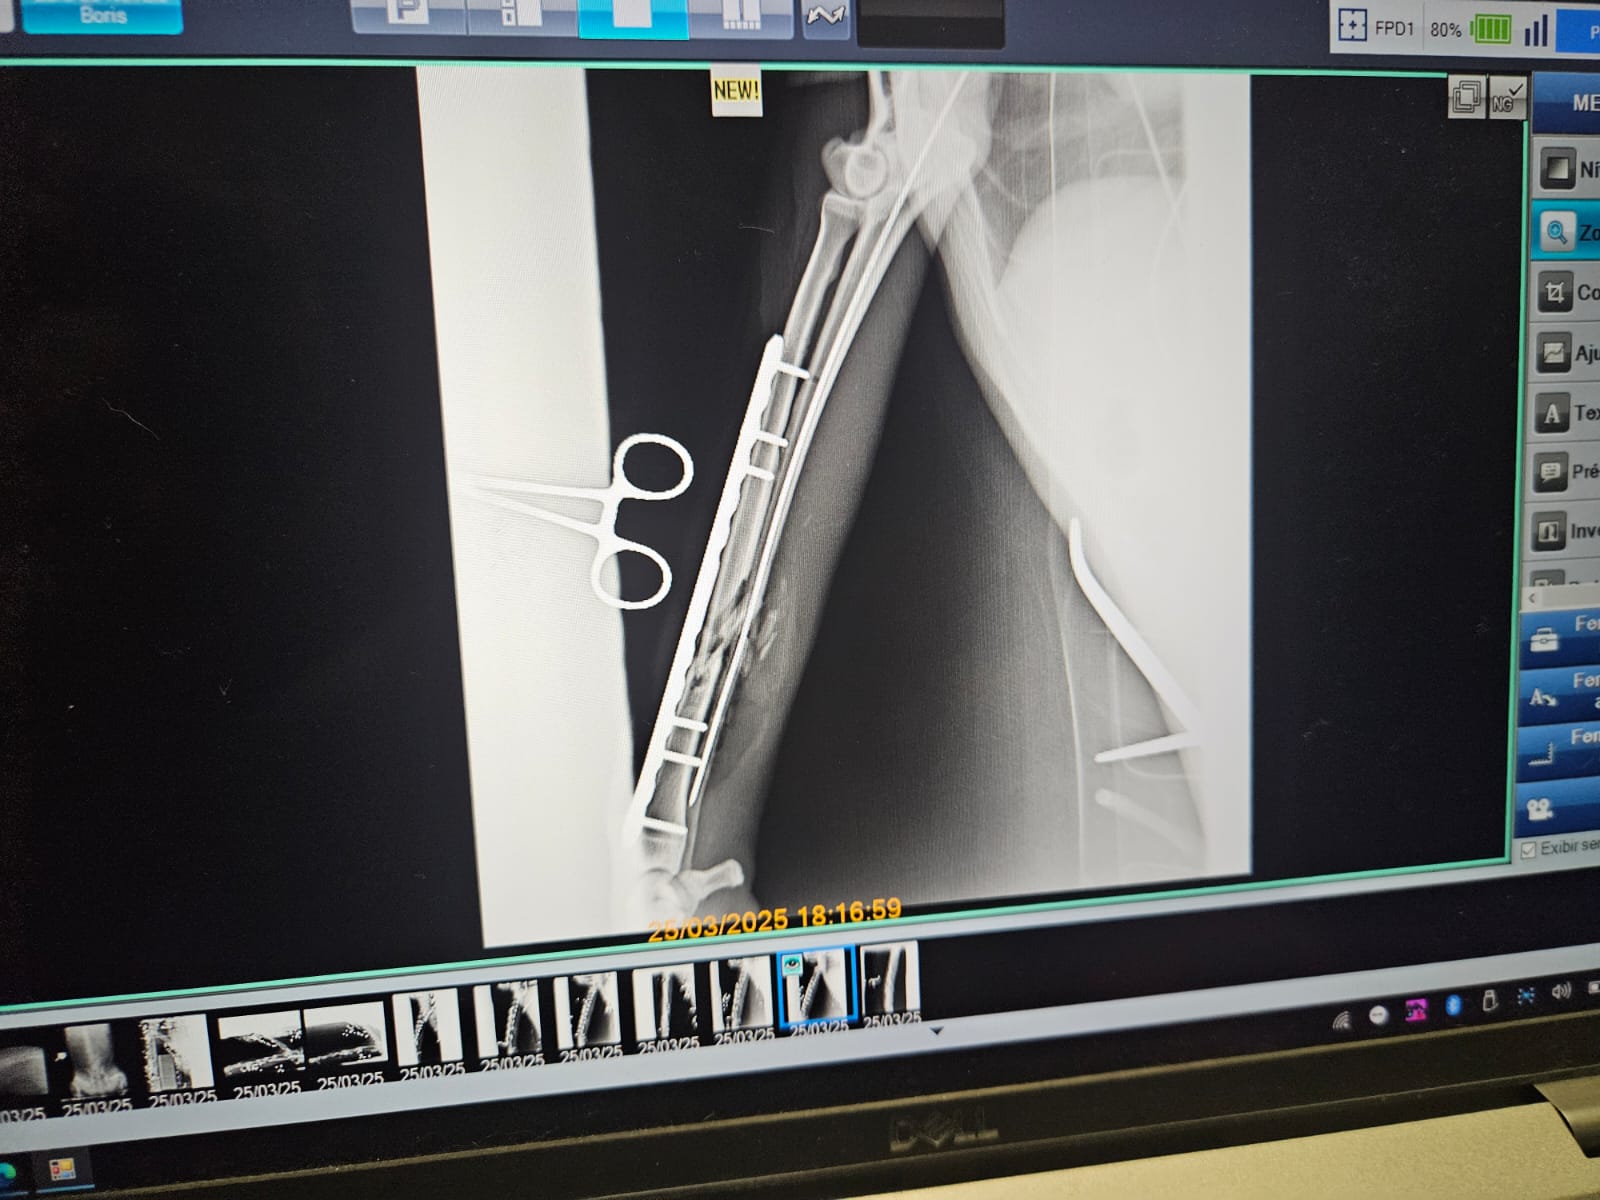

O médico veterinário e coordenador de Gestão de Fauna do Inema, Vinícius Dantas, explicou sobre as medidas clínicas adotadas. “Após estabilização do estado clínico, o indivíduo atendido no Parque Vida Cerrado precisou ser transferido para o Cetas, na capital baiana, onde constatamos a necessidade de intervenção cirúrgica nas duas patas dianteiras, uma ação para que o animal recupere suas funções de locomoção. A intervenção foi um sucesso, o animal respondeu muito bem aos procedimentos realizados, tendo um excelente pós-operatório e agora passará pelos cuidados de uma equipe multidisciplinar, que dará continuidade ao tratamento e processo de reabilitação”.

A operação ocorreu com o apoio do Instituto de Cirurgia Ortopédica e Neurológica Veterinária (ICONVET), que disponibilizou seu centro cirúrgico localizado no bairro do Rio Vermelho, com todos os equipamentos e suporte de profissionais com experiência em veterinária ortopédica.